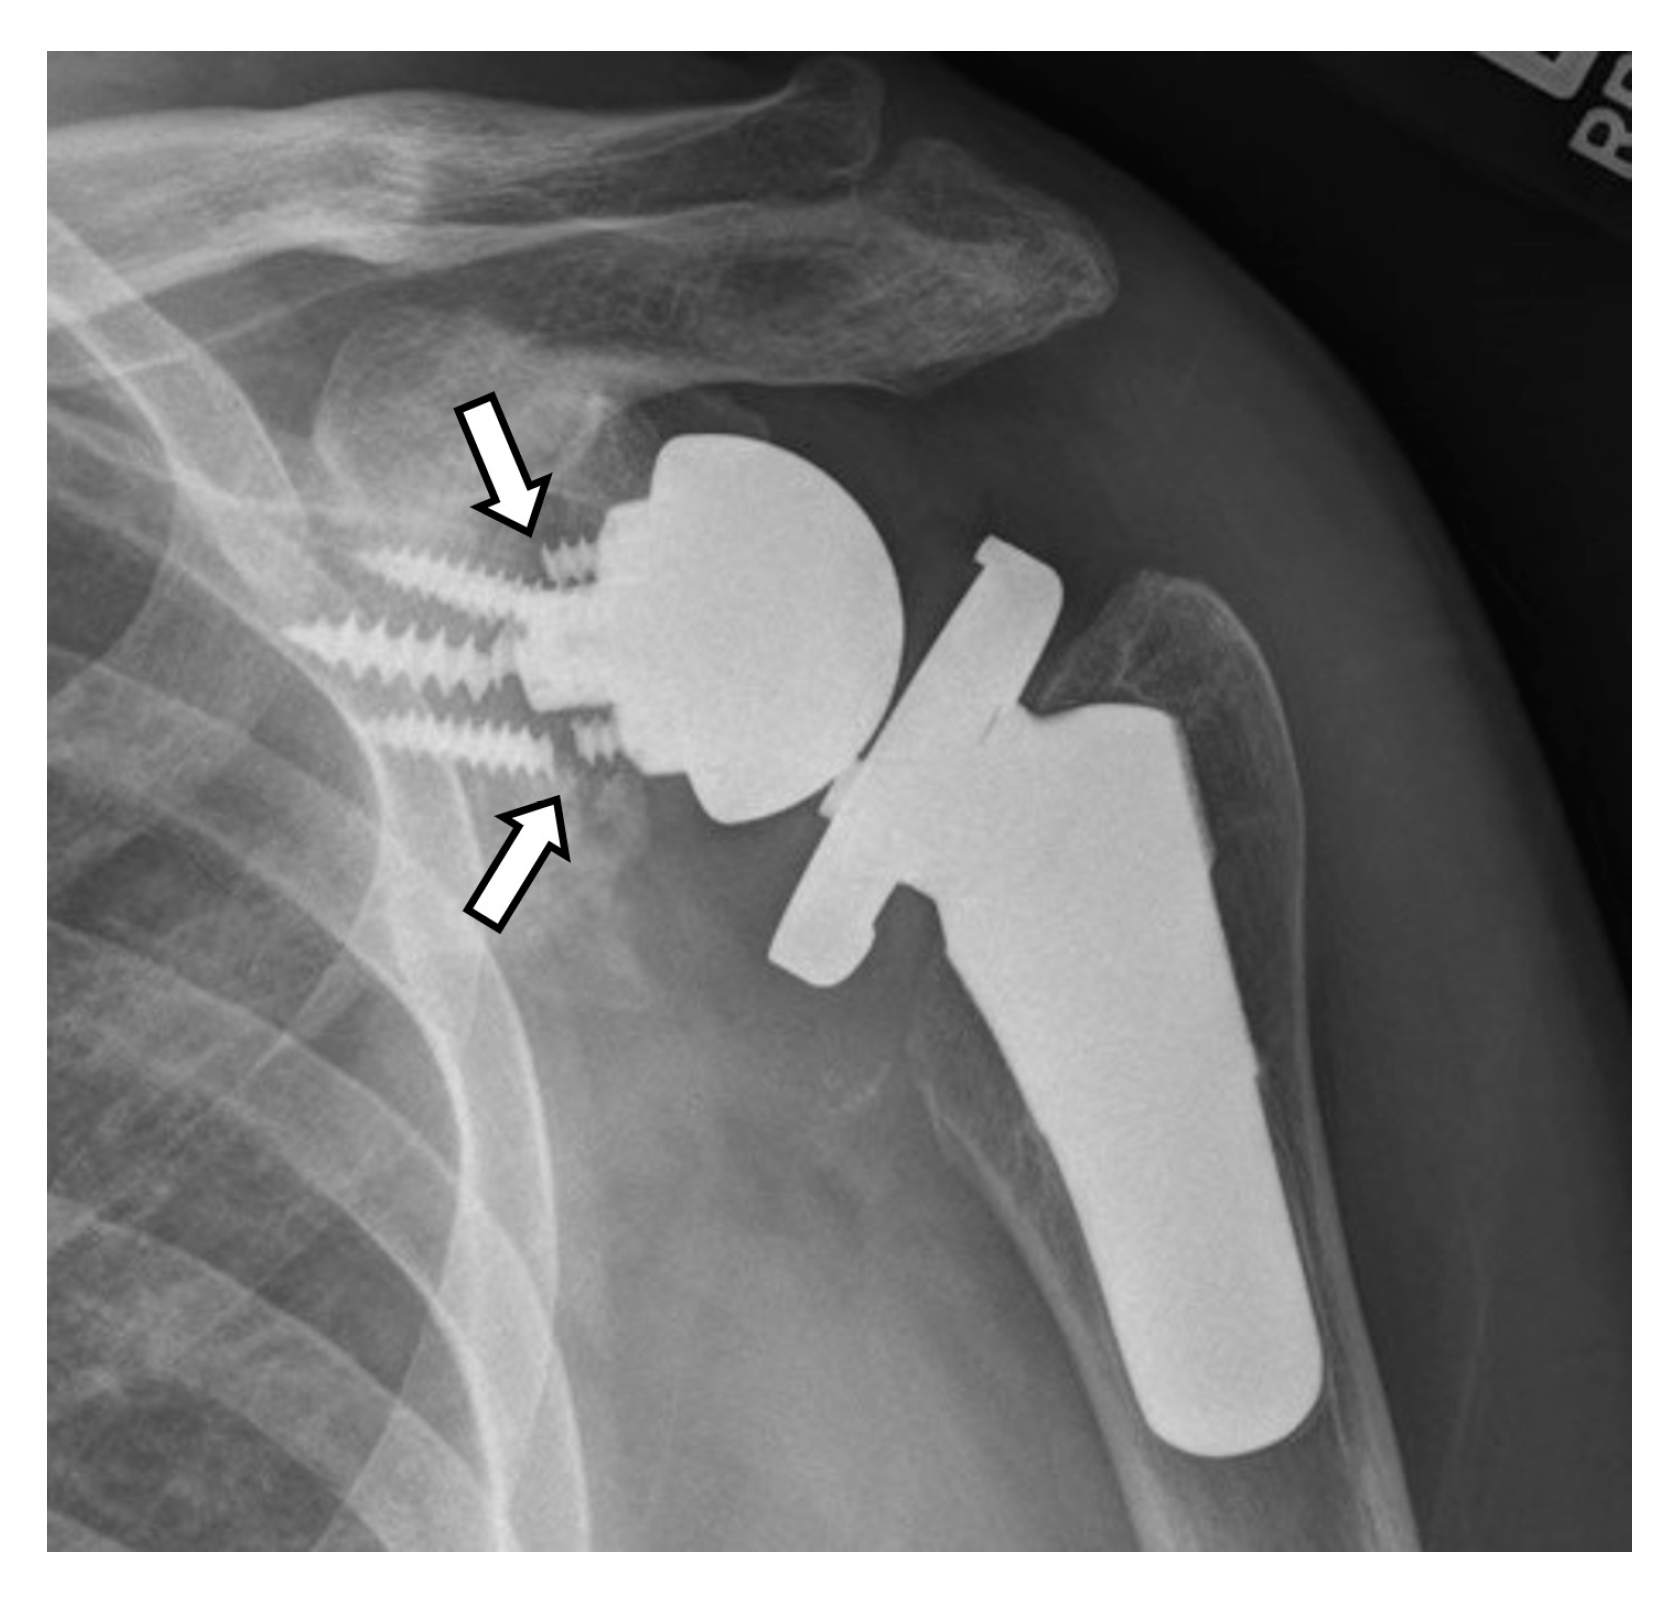

4.2.1. Loosening and Hardware Dissociation

5.1.1. Humeral Head Resurfacing/Stemless Hemiarthroplasty (HHRA)